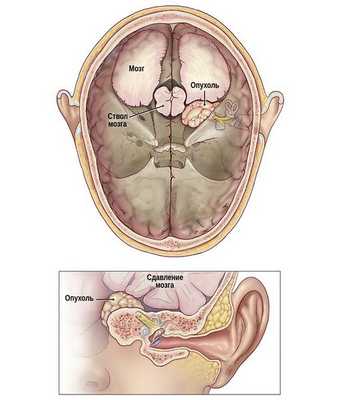

Рис. Схематичное изображение роста невриномы слухового нерва из внутреннего слухового прохода в заднюю черепную ямку со сдавление ствола головного мозга.